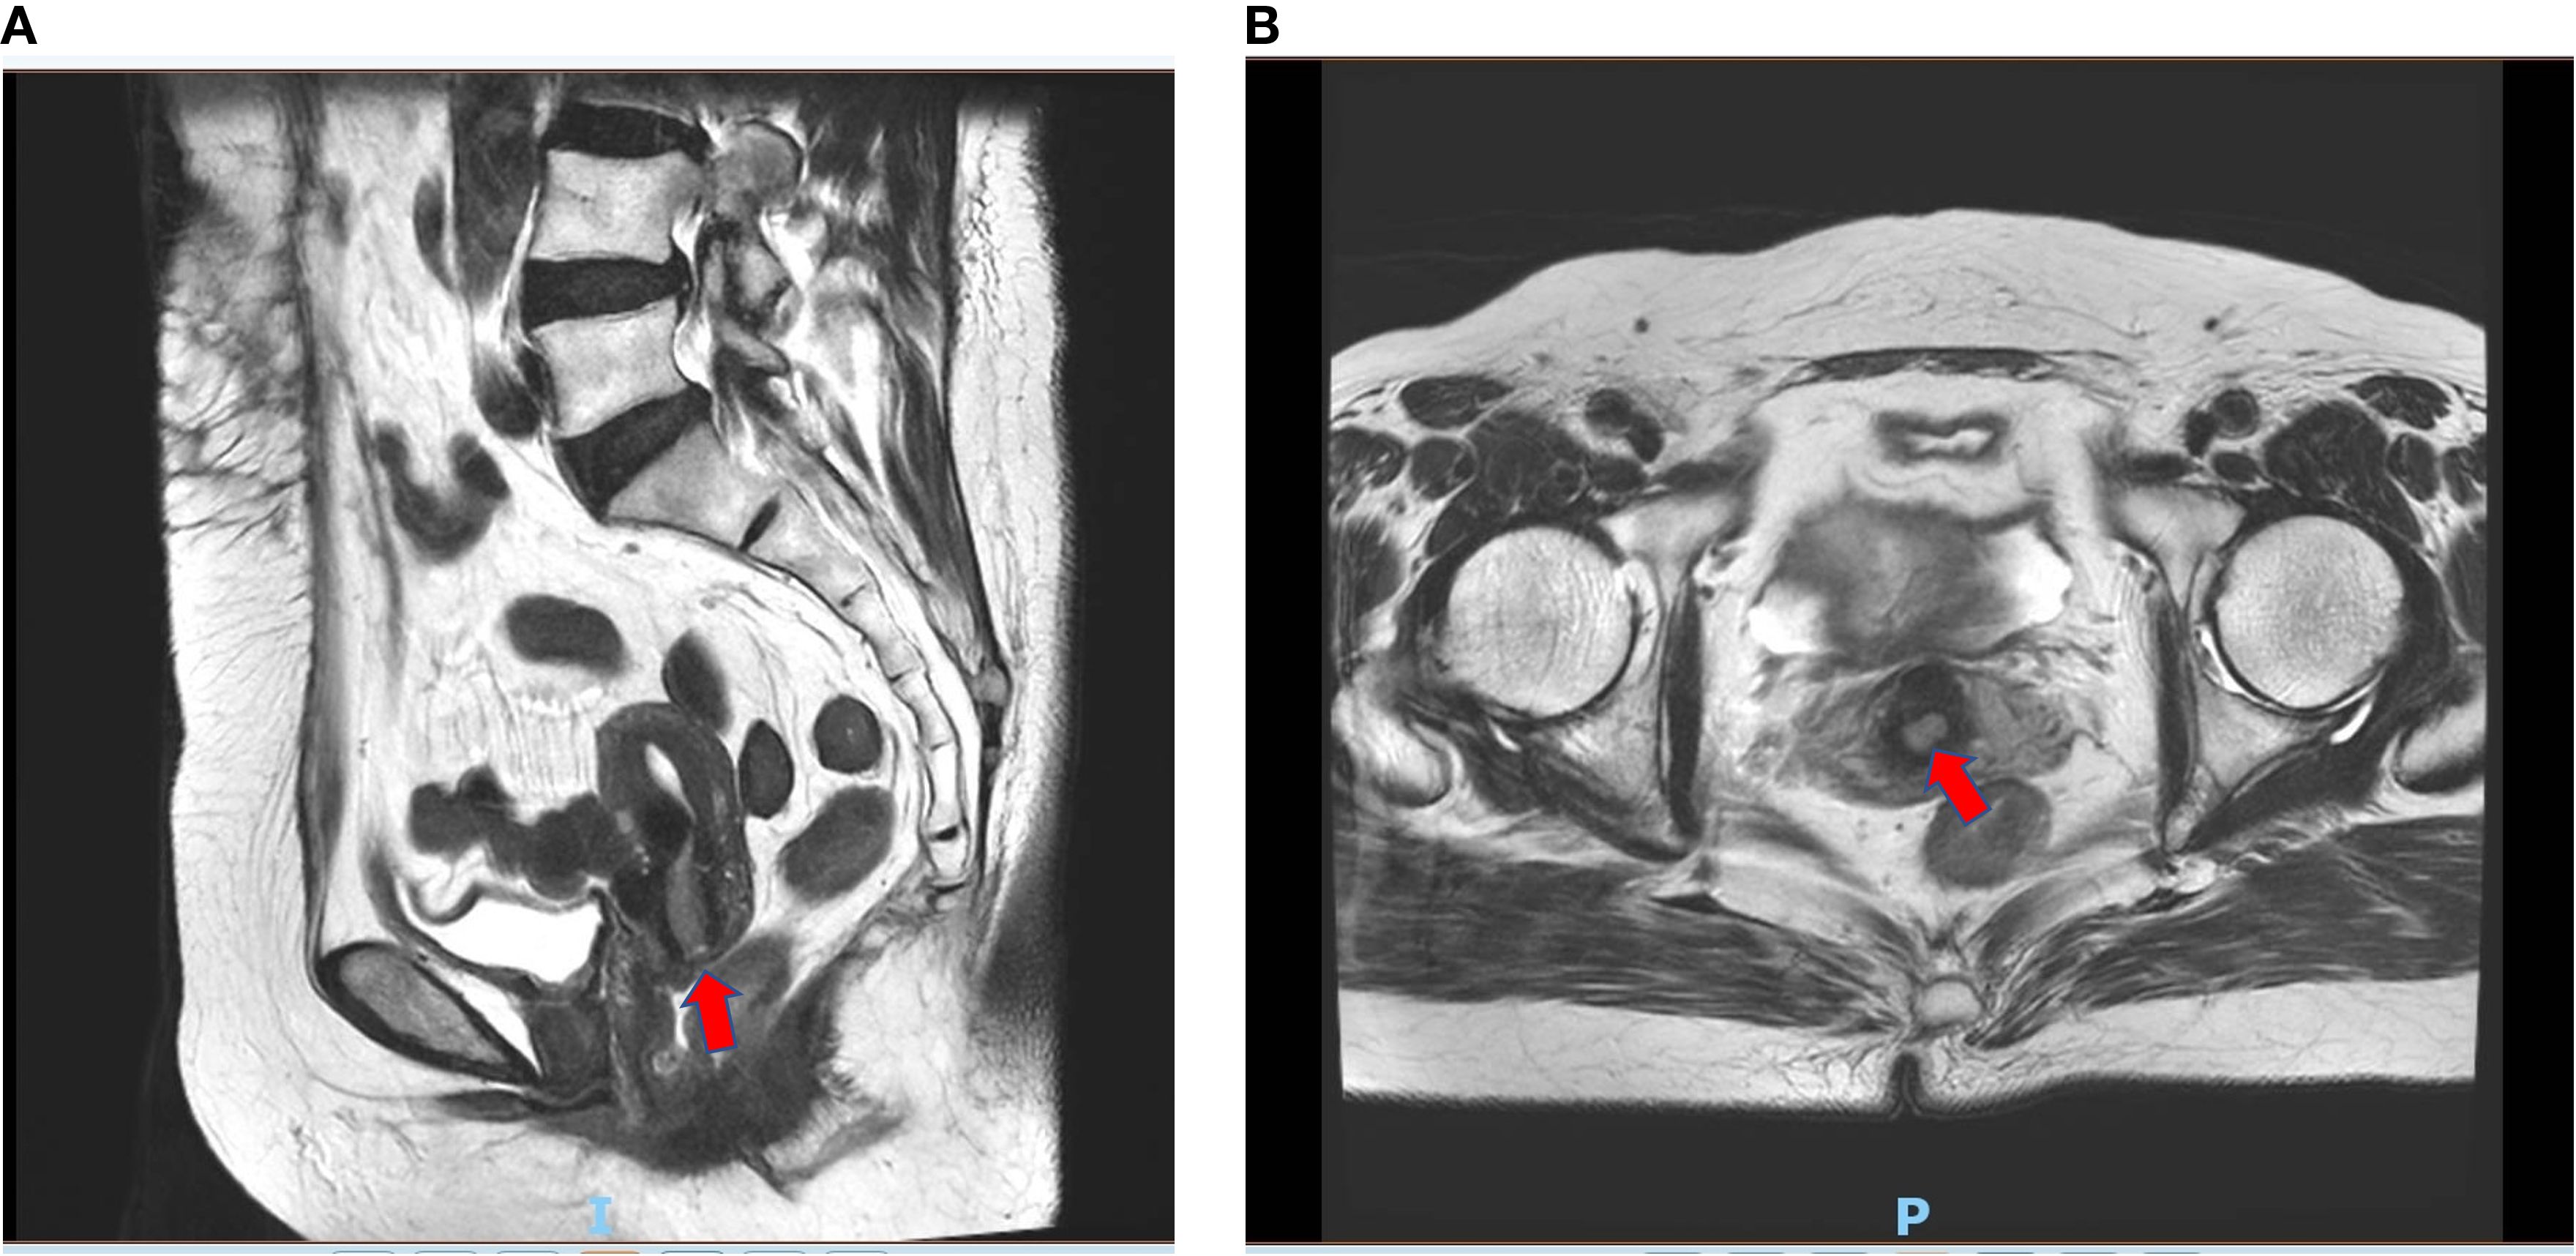

Pelvic enhanced magnetic resonance imaging showed a thickened mucous membrane of the cervical canal, which was a patchy long T1 and long T2 signal lesion and measured approximately 12 mm × 8 mm × 18 mm. The lesion exhibited a high signal on diffusion-weighted imaging (DWI) and a strong enhancement, with a continuous low signal at the local cervical junctional zone. The images are presented in Figure 4. However, on April 3, 2024, a gynecologic examination and colposcopy did not find any abnormalities. The cervical pathology displayed in Supplementary Figure S1 suggested atrophic signs, and the high-risk human papillomavirus (HPV) subtypes were all negative.

Text  Two MRI scans showing pelvic anatomy. In both images, red arrows highlight suspected cervical lesion. The left image 'a' is a sagittal view; and the right image 'b' is a transverse view of the pelvis.

Figure 4. Enhanced magnetic resonance imaging of suspected cervical lesion on April 20th 2024. (A) Sagittal view of enhanced magnetic resonance imaging of suspected cervical lesion on April 20th 2024. (B) Axial view of enhanced magnetic resonance imaging of suspected cervical lesion on April 20th 2024.